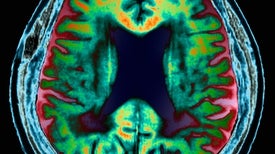

Research suggests that the family of hormones has a crucial role in the hippocampus

Blocking an immune-related molecule lodged in blood vessels stops memory loss

A new algorithm accurately identified more than 90 percent of people who would advance to an Alzheimer’s diagnosis in about six years